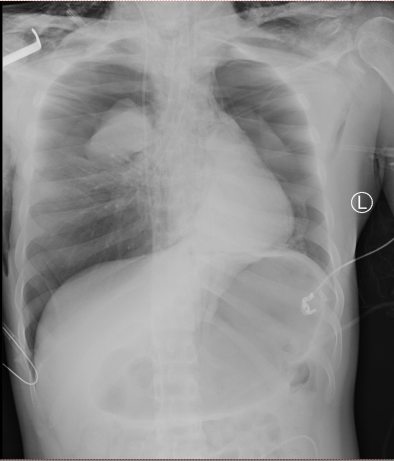

患者入院时虽神志尚清,但已出现声音嘶哑、颈部疼痛、胸闷气喘等危险信号,血氧饱和度持续下降。我院急诊团队评估后立即启动最高级别预警,迅速完成生命体征监护和检查的同时,敏锐地察觉到患者颈部正在快速肿胀,这是皮下气肿的典型表现,预示着气道可能存在严重破损。我院耳鼻喉科专家通过喉镜探查,做出了关键性判断:高度怀疑喉软骨骨折、气管断裂。后续CT检查结果印证了这一判断,患者双侧颌面部、颈部、胸部乃至纵隔内出现了大量积气。更危急的是,断裂处漏出的气体已形成双侧张力性气胸,双肺被压缩均近50%,心脏和大血管严重受压,情况十分危急!